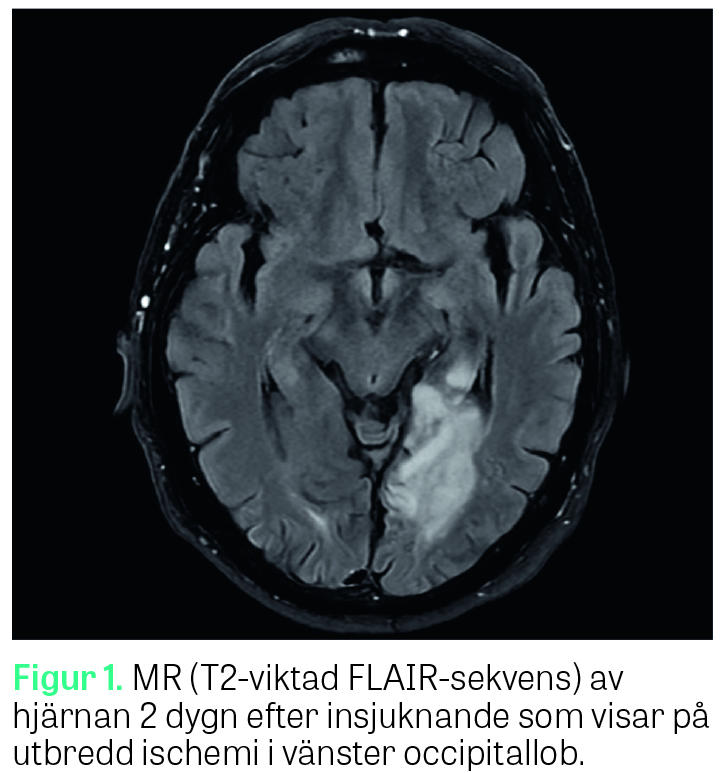

Vid klinisk undersökning på avdelningen av neurolog ett dygn senare var patienten generellt välmående. Han var helt orienterad och uppskattades till RLS 1/GCS 15. Inga motoriska eller sensoriska avvikelser uppdagades. Patienten påtalade att han märkt att han hade svårt att se på sin högra sida, vilket även konfirmerades vid Donders test då en högersidig hemianopsi upptäcktes. Patienten var dock fullt medveten om sin synfältsdefekt och märkte själv hur han kunde kompensera för den genom att vrida huvudet något extra åt höger då han till exempel tittade runt i rummet; således förelåg ingen visuell neglekt. Vid test av läsförmåga förevisas patienten korta »datorskrivna« ord och fraser på ett papper (Riksstrokes manual för NIHSS, National Institutes of Health stroke scale) som hen ska läsa högt. Vid första försöket tolkade patienten orden som siffror, och i stället för att läsa upp till exempel »Du kan«, »Jordnära« och »Jag kom hem från arbetet« läste han »fyra, sju, fem, fyra« etc. Då detta påtalades för patienten gjordes ett nytt försök, och då läste patienten i stället bokstäverna var för sig (»d«, »u«, »k«, »a« etc.). Patienten ­stakade sig ­något vid uppläsningen då han behövde tänka ­efter, men hade inga bekymmer att känna igen bokstäverna efter en stunds betänketid. Det förelåg dock en fortsatt svårighet att sammanfoga bokstäverna till ord. Vid undersökning av skrivförmåga med papper och penna kunde patienten utan bekymmer skriva till exempel »Jag befinner mig på lasarettet« och »Det är februari månad« med både bevarad stavning och handstil. Då patienten direkt efteråt ombads att läsa upp vad han själv skrivit återgick han till att stakande läsa upp bokstäverna var för sig (så kallad »letter by letter reading«) utan att kunna sammanfoga dem till ord. Undersökningen upprepades ett antal gånger för att säkerställa att det inte var patientens högersidiga synfältsdefekt som gjorde att han inte kunde läsa från vänster till höger, men samma mönster upprepades oavsett var i synfältet texten placerades. Patienten kunde på ett adekvat sätt förmedla var i synfältet han hade svårt att se och visade själv hur han kompenserade för detta. Diag­nosen alexi utan agrafi misstänktes och MR hjärna genomfördes som visade på infarktförändringar i vänster (dominant) occipitallob med engagemang av splenium corporis callosum och posteriora talamus (Figur 1–3), överensstämmande med vad man kunnat se i tidigare fallbeskrivningar av alexi utan agrafi [1, 2]. Under vårdtiden uppdagades ett förmaksflimmer på telemetri, vilket bedömdes vara genesen till patientens stroke. Patienten påbörjade behandling med antikoagulantia för att minska risken för ytterligare tromboembolism, erhöll remiss till logoped för att få hjälp med att träna upp läsförmågan och skrevs ut väsentligen välmående från lasarettet ett par dagar senare.

Syndromet alexi utan agrafi (eng: pure alexia), beskrevs av den franske neurologen Joseph Jules Dejerine redan 1892 [3] och i ett flertal fallrapporter därefter [1, 2, 4]. Alexi utan agrafi hör till gruppen »disconnection syndromes«, vilka kan uppstå av skador på nätverken mellan hemisfärerna eller mellan olika delar inom samma hemisfär [5]. De flesta beskrivna fall av alexi utan agrafi har berott på cerebrala infarkter orsakade av ocklusion i arteria cerebri posterior på den dominanta, oftast vänstra, sidan med resulterande infarkt i vänstra visuella kortex och splenium corporis callosum. Förklaringen till fenomenet är att lesionen i splenium stör kopplingen mellan den högra, icke-dominanta sidans visuella kortex och den dominanta sidans gyrus angularis, som med sitt läge i omedelbar anslutning till Wernickes språkförståelse­area har en avgörande betydelse för vår läsförmåga. Den bevarade skrivförmågan förklaras av att den dominanta gyrus angularis i sig själv lämnas intakt vid denna skadelokalisation [1, 6]. Utöver infarcering orsakad av ocklusion i arteria cerebri posterior har syndromet även kunnat ses vid glioblastom [7] och multipel skleros [8].